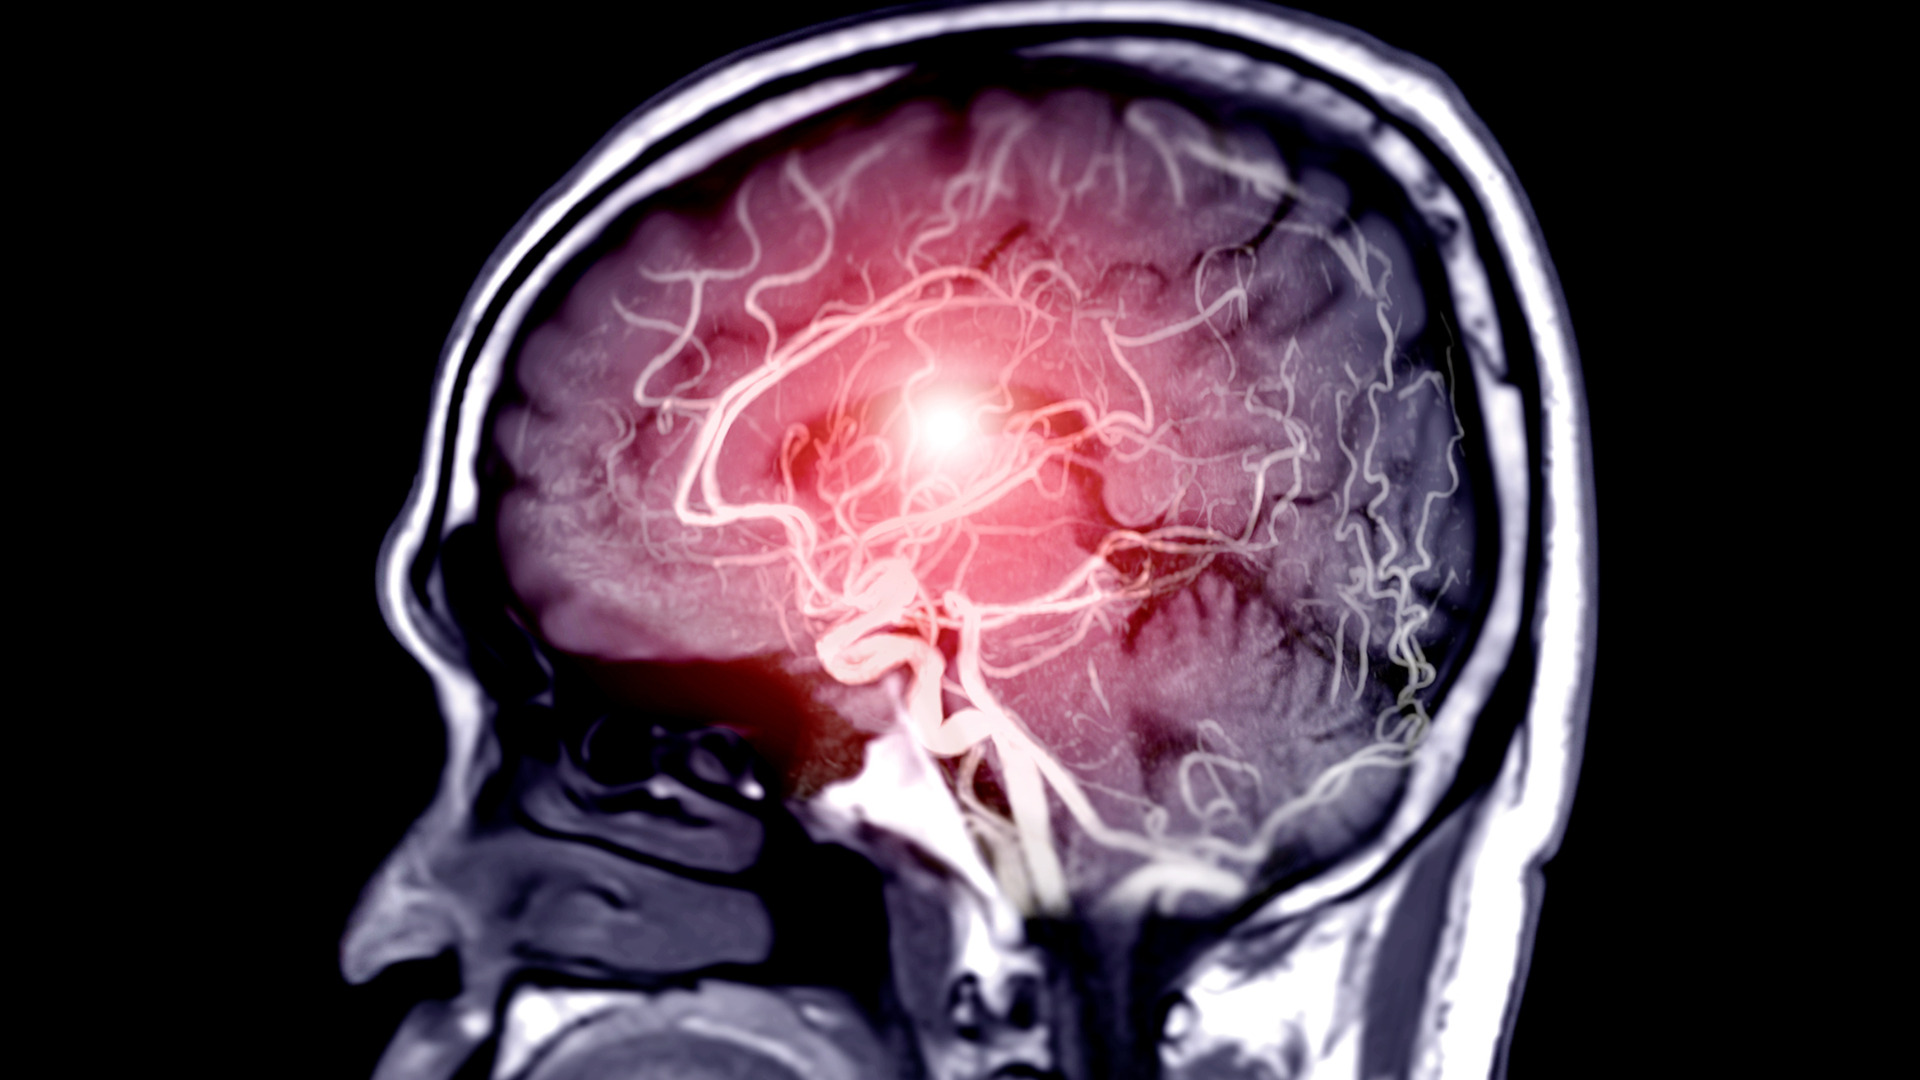

Tăng áp lực nội sọ là một biến chứng nặng gặp ở bệnh nhân đột quỵ (tai biến mạch máu não)

Tăng áp lực nội sọ là một biến chứng nặng gặp ở bệnh nhân đột quỵ (tai biến mạch máu não)